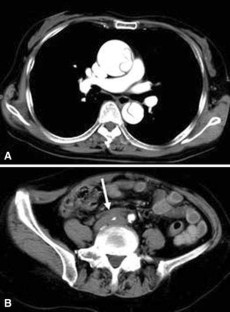

A 75-year-old female was admitted to our hospital with sudden back pain and right leg ischemia. Computed tomography showed acute type A aortic dissection with the occlusion of the right common iliac artery. The patient was treated with ascending aorta replacement and femoro-femoral bypass. Three hours after the operation, the patient went into a sudden shock. Electrocardiogram showed ventricular tachycardia and ventricular fibrillation. Percutaneous cardio-pulmonary support was administered and coronary arteriogram (CAG) was proceeded for evaluation of the coronary arteries. Although CAG revealed normal coronary arteries, intravascular ultrasound showed mobile intimal flap at left main coronary artery trunk, suggesting dissection of the coronary artery. Percutaneous coronary intervention of the left main coronary artery trunk was performed. The patient recovered from shock and was discharged from the hospital without any major complication.

Fig. 2